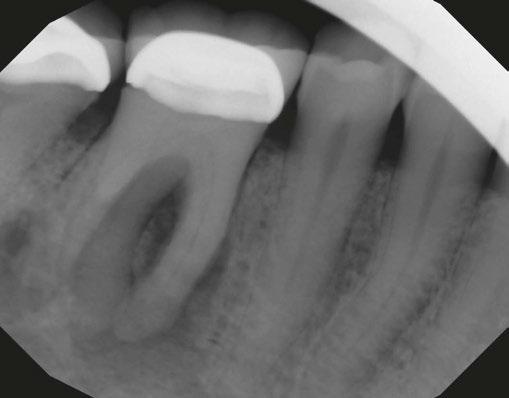

Figures 3A-3E: 3A Periapical radiograph of the dens in dente. It is impossible to determine the accurate source of infection. 3B. Hedstrom file in the invagination. 3C. Files

int the C-shaped main canal. 3D.The obturated enamel of lined canals with Biodentine. The radiopacity is similar to that of dentin. 3E. Healing of the periapical lesion in the 3-year follow-up and continued root formation